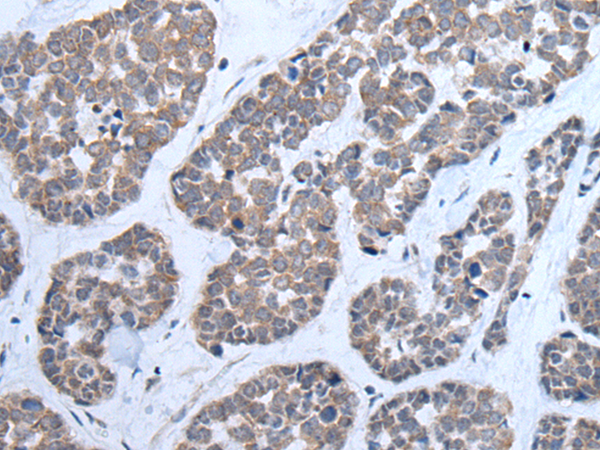

分类: 科研抗体货号: P12810别名: PSA; SGPA; ZNF912应用: WB,IHC反应种属: Human, Mouse, Rat